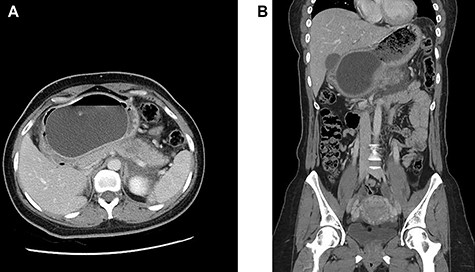

(A and B) Axial and coronal intravenous contrast-enhanced computed tomography images of the abdomen and pelvis showing an IGB compressing the pancreatic body with resultant pancreatic interstitial oedema and peri-pancreatic fluid collection.

Intravenous contrast-enhanced computed tomography of the abdomen, pelvis was done (Fig. 2), and it showed an intra-gastric balloon compressing the pancreatic body with resultant ill-defined hypodensities noted at the pancreatic body and surrounding peri-pancreatic fluid collection suggestive of acute interstitial pancreatitis. No cholelithiasis, intrahepatic or extrahepatic biliary dilatation was seen.